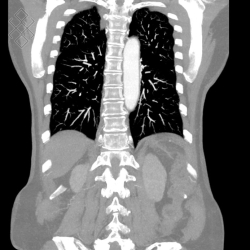

Angio-IRM Thoracique

Vous entrez dans l'aimant, ouvert des 2 côtés, la tête la première et allongé sur le dos. Pour recueillir le signal et contruire les images, vous aurez une antenne sur le thorax. Étant donné que cet examen est bruyant, vous aurez à votre disposition des tampons auriculaires pour atténuer le bruit de la machine et écouter les consignes du manipulateur en radiologie.

La durée moyenne de l'examen est de 30 min. Dans le cas d'une injection, le manipulateur en radiologie vous administrera le produit de contraste. Vous entendrez un bruit caractéristique à l'IRM faisant penser à un marteau piqueur.